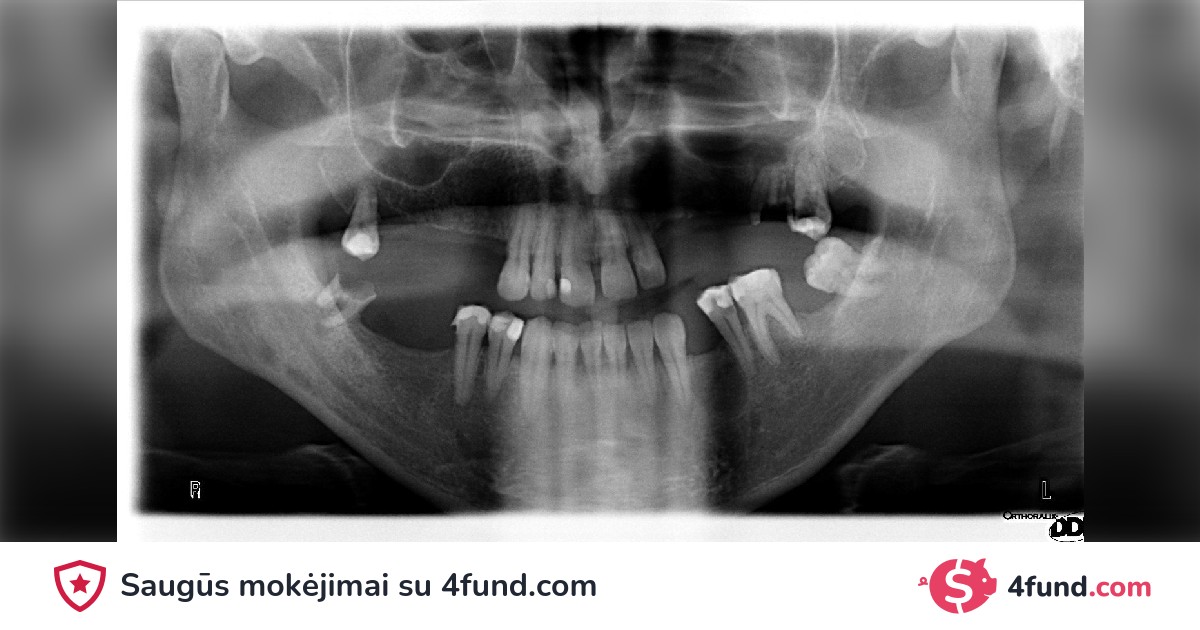

Over the years, I have faced oral health challenges that have made my life a journey of pain and embarrassment. Dental problems have not only affected my self-esteem but also my overall health, becoming a daily battle that I cannot win alone.

As far back as I can remember, I have had issues with my teeth. Unfortunately, due to financial limitations, postponing treatment was my only option. This delay has caused significant damage, and I now face a series of serious dental complications.

My necessary dental treatment includes surgeries, extractions, implants, and extensive dental restorations. The cost of these procedures is significant and is beyond what I can afford on my own. That is why I am turning to you, the community, and friends to help me restore my oral health and, with it, my self-esteem and quality of life.